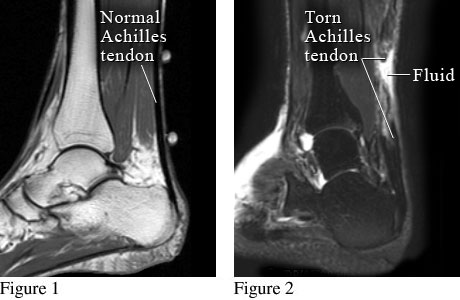

Courtesy of Intermountain Medical Imaging, Boise, Idaho.

Figure 1 shows magnetic resonance imaging (MRI) of a normal heel and Achilles tendon. Figure 2 shows a torn Achilles tendon with fluid collected at the site of the tear.